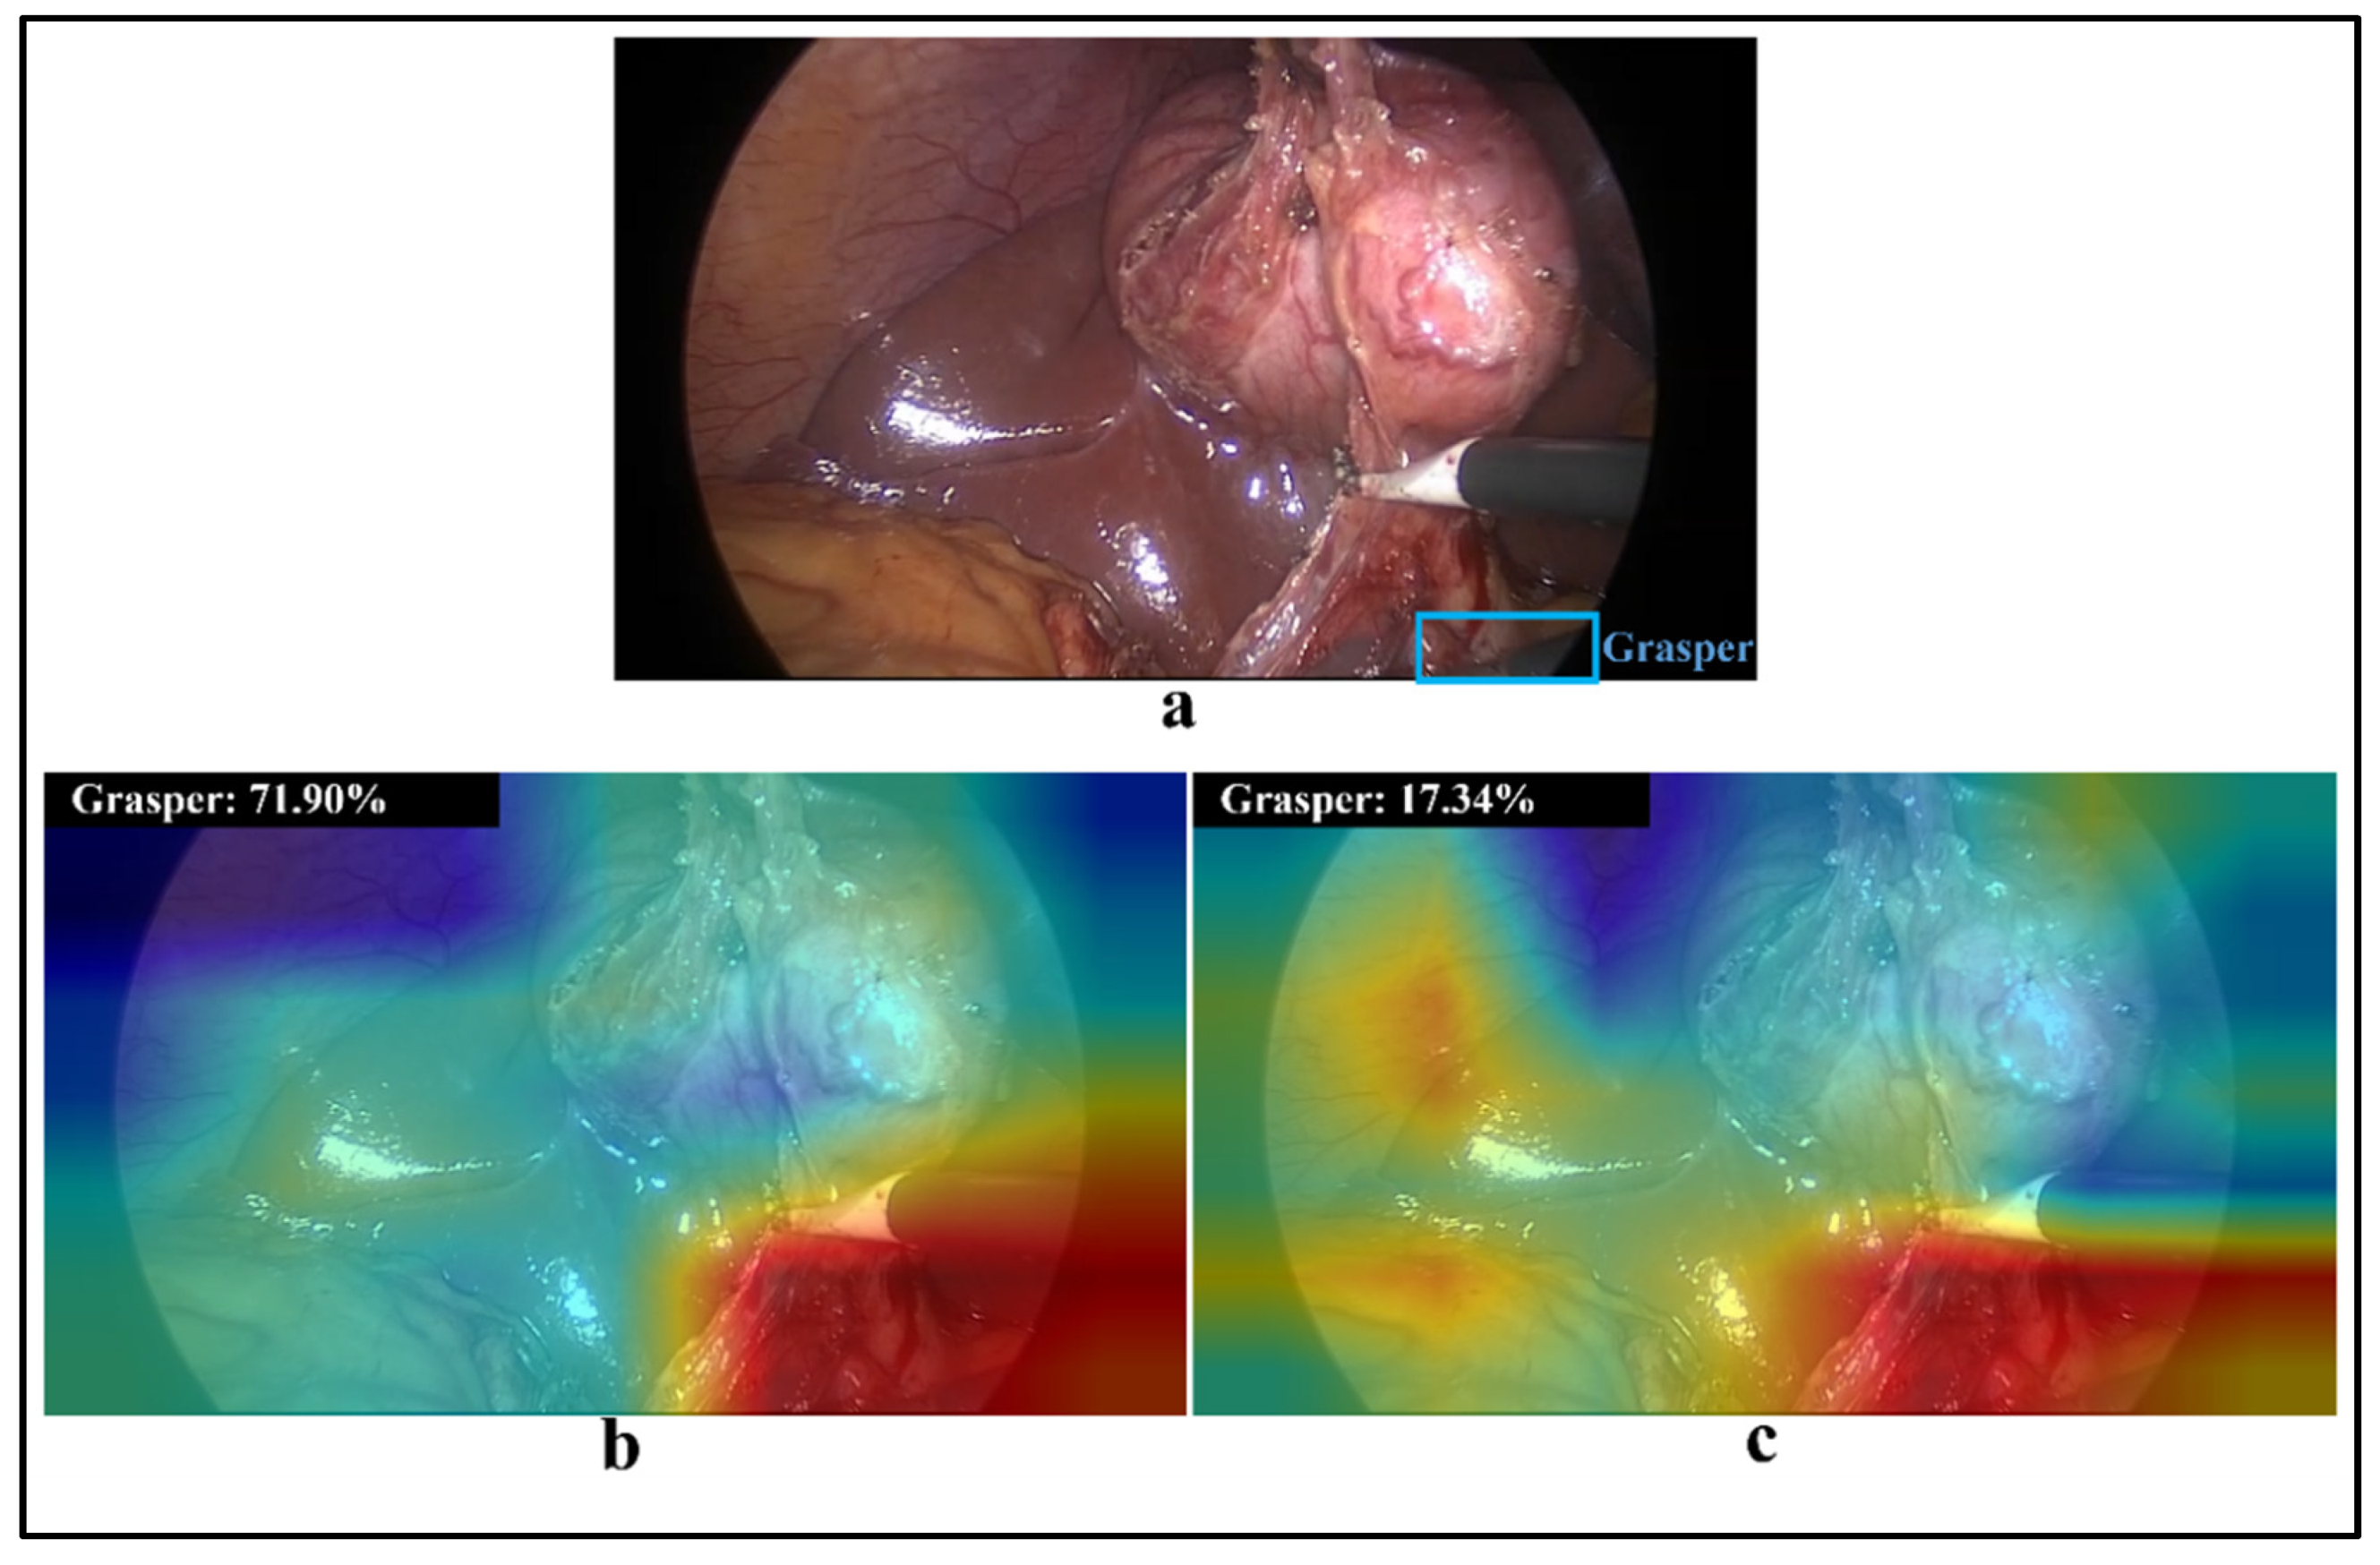

- Selvaraju, R.R.; Cogswell, M.; Das, A.; Vedantam, R.; Parikh, D.; Batra, D. Grad-cam: Visual explanations from deep networks via gradient-based localization. In Proceedings of the IEEE international Conference on Computer Vision, Venice, Italy, 22–29 October 2017; pp. 618–626. [Google Scholar]